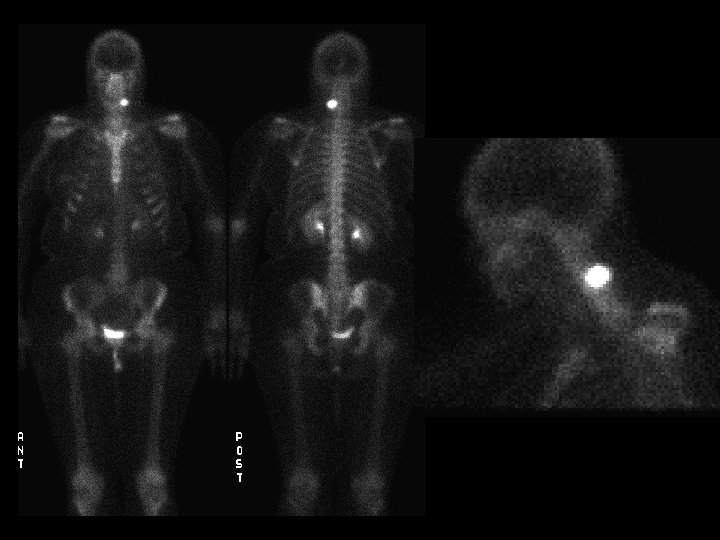

Osteopetrosis Tc99 m sulfur colloid i v intense

Osteopetrosis • • • Tc-99 m sulfur colloid, i. v. intense liver/spleen uptake, little or none in the bone marrow Trabecular --> compact bone --> Diffuse inc bone density Anemia w/extramedullary hematopoiesis ddx: (adults) – – – myelofibrosis sclerotic metastases renal osteodystrophy multiple myeloma Paget’s